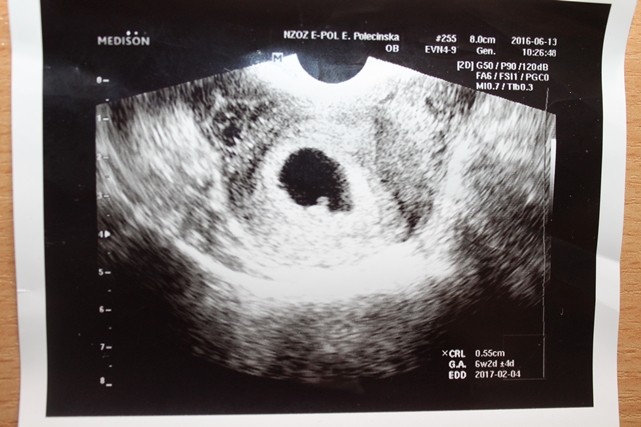

hej dziewczyny byłam dzisiaj na wizycie serduszko ładnie bije dzidziuś ma 0,55 cm wszystko się zgadza według OM. :biggrin2::biggrin2::biggrin2::biggrin2::biggrin2::biggrin2::biggrin2::biggrin2::biggrin2:

• IMG_8222.JPG

74,9 KB · Wyświetleń: 92